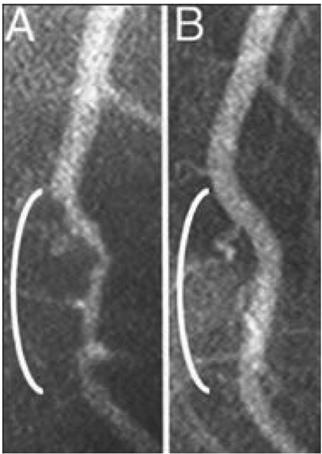

Например, при определенных типах питания можно отсрочить или даже предотвратить опасные для жизни сердечно-сосудистые заболевания. На рентгеновских снимках (рис. 02) можно проследить, как массивные заторы в кровеносных сосудах сами собой растворяются, превращаясь в ничто.

Рис. 0.2. Оба рентгеновских снимка показывают участок левой коронарной артерии, которая снабжает кровью большую часть сердца. Слева (A) можно увидеть больной сосуд (белая «трубка», которая выглядит как ветка и проходит сверху вниз, – обратите внимание на сужение в области белой скобки, как будто трубка сдавлена, что замедляет кровоток). На правой картинке (B) показан тот же самый сосуд после 32 месяцев строгой вегетарианской диеты, при которой пациент питался исключительно растительной пищей. Сужение исчезло, кровоток восстановился, артерия вновь выглядит совершенно здоровой. Болезни сосудов можно не только приостановить, но даже обратить вспять, и все это без хирургического вмешательства и медикаментозного лечения[11].

Подобные факты подтверждают невероятную силу питания, которую мы можем контролировать самостоятельно – она буквально в наших руках. Результаты показывают, насколько основательно и глубоко можно улучшить жизнь, просто изменив рацион питания.